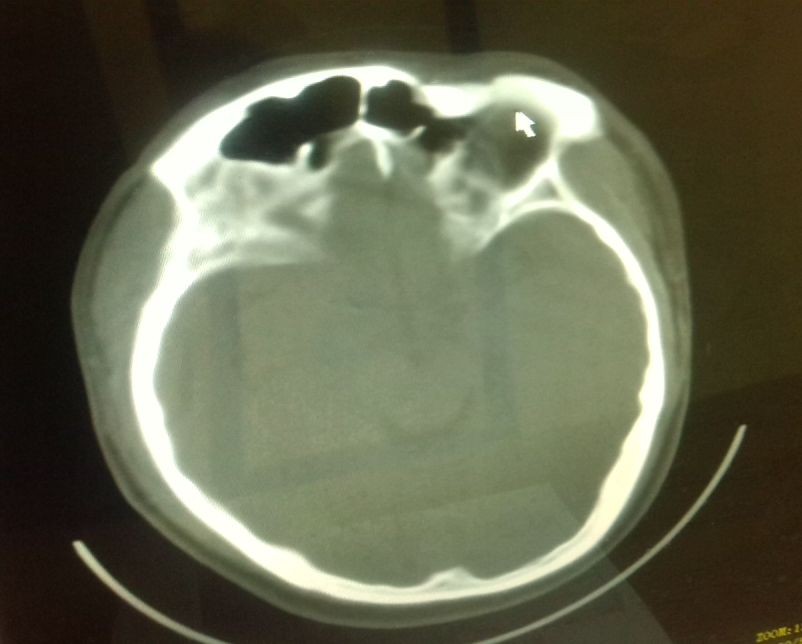

[attachmentid=323747] 颅骨被打破裂!

昨晚承包老板、村干部召开全体村民会议,在会议过程中,竟然发生了令人意想不到的重大情况:现任村长及前任村长竟然对村民大打出手,甚至追到村民的家中,拿东西将一位村民的头都打破了,连去救架的都被打!被打伤的村民现在医院留医!

昨天村民自发凑钱给伤者住院治疗!

伤者家庭经济很困难,希望派出所早日结案,把打人者绳之以法!